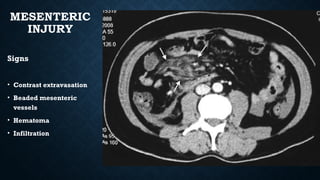

MESENTERIC

INJURY

Signs

• Contrast extravasation

• Beaded mesenteric

vessels

• Hematoma

• Infiltration